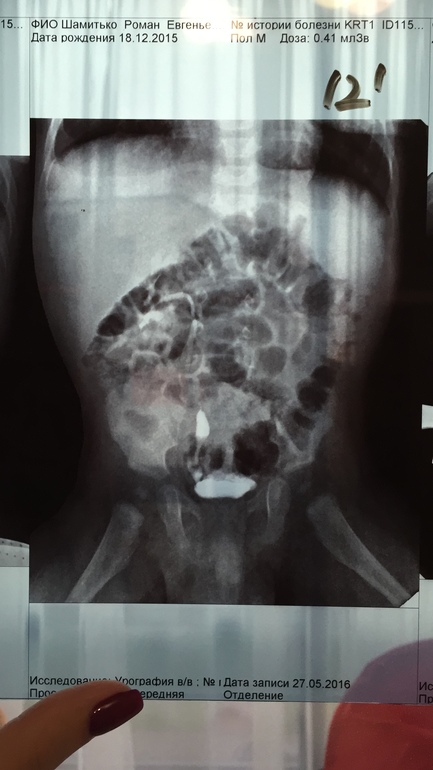

Мультикистоз почки

Да, почка "немая" там нет функции

Вероятно облитерация сосудов не полная и они поддерживают почку